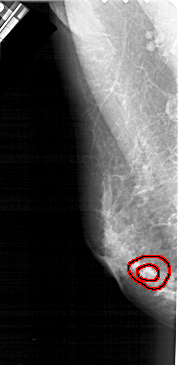

A_1938_1.RIGHT_CC

RIGHT_CC LINES 4366 PIXELS_PER_LINE 1876 BITS_PER_PIXEL 12 RESOLUTION 43.5 NON_OVERLAY